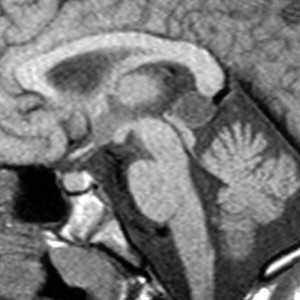

Проведено МРТ головного мозга — заключение: «очаг ишемии в левой лобно-теменной области на фоне сосудистых аномалий». Очаг измененной интенсивности сигнала показан на рис. 4 (верхний ряд, правые снимки); «сосудистая аномалия» заключалась в умеренном сужении проксимального сегмента левой средней мозговой сонной артерии, сразу после отхождения от внутренней сонной артерии (не показано за неимением места в тексте статьи). На приведенных изображениях (рис. 4) отчетливо виден симптом «клубка в разрезе».

В течение месяца состояние пациента остается прежним, без клинической динамики. Анализы крови, биохимия — без патологии. МРТ головного мозга от 25.08: «МР-картина нарушения мозгового кровообращения в бассейнах левых средней и задней мозговой артерий в подострой стадии по ишемическому типу» (рис. 4, правые снимки верхнего ряда). Имевшееся сегментарное сужение левой средней мозговой артерии остается без динамики (не показано за неимением места в тексте статьи).

Симптом туннеля (специфический симптом!) вдоль стенки левого бокового желудочка от лобной доли в затылочную трактовки не получает. Очаг корково-подкоркового отека с геморрагией в левой гемисфере, соответствующий некротизирующему васкулиту [11, 12], — ситуация, давно известная при гельминтозах [6], трактовки не получает. На представленных снимках гельминт уже не визуализируется (погиб), но имеется текущее воспаление (в теменной, затылочной областях мозга), на которые можно и должно воздействовать — кортикостероиды парентерально.

На МРТ головного мозга картина очагов локальной атрофии в лобной, теменной и затылочной долях слева, сохраняется линейная атрофия на месте хода нематоды из лобной доли в затылочную (туннель) (рис. 4, нижний ряд). Имевшееся сегментарное сужение проксимальной части левой средней мозговой артерии сохраняется без динамики. Степень расстройства функции (теперь уже невзирая на данные МРТ) не позволяет надеяться на клиническое восстановление, пациент обречен на инвалидизацию…